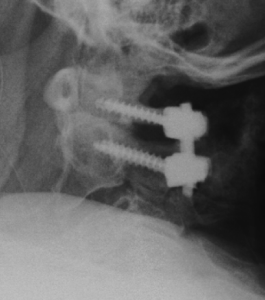

Beim zervikalen Bandscheibenvorfall wird in der Regel die Bandscheibe mit einem Platzhalter ersetzt, nachdem diese unter dem Mikroskop vollständig entfernt wird.

Zeigt sich ein höhergradiger Verschleiß bzw. eine ausgeprägte Instabilität, wird der betroffene Wirbelsäulenabschnitt versteift (Fusion). Kombiniert mit diesem Verfahren kann ggf. auch eine Erweiterung des Wirbelkanals (Dekompression) bei Verengung (Spinalstenose) erfolgen.

Wirbelkörperersatz

Bedingt durch eine Entzündung, einen Bruch oder eine Tumorerkrankung kann ein Wirbelkörper vollständig zerstört werden. Durch einen Platzhalter wird der betroffene Wirbelsäulenabschnitt rekonstruiert und stabilisiert.